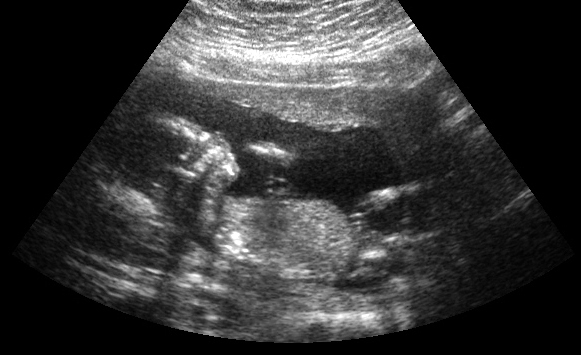

I recently had a 16 week ultrasound. Unfortunately, baby wasn't very cooperative (no potty shot) and the technician said although she couldn't be certain, she was "leaning towards boy." I have this photo which is a profile pic, however, the baby seems to be turning towards the front.

Attachment 21653

Do you think the technician is leaning in the right direction?